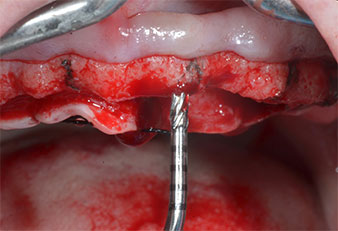

Uno strumento piezoelettrico (Piezomed I1) a forma di fiamma, rivestito in diamante, è stato usato per contrassegnare le posizioni dell'impianto e per eseguire una preparazione pilota (Fig. 3). Si è prestato attenzione a utilizzare un movimento verticale ascendente e discendente, con potenza ridotta, irrigazione completa e bassa pressione (inferiore a 300 g). Successivamente è stato applicato uno strumento pilota (Piezomed I2A/I2P) per l'ingrandimento iniziale delle sedi dell'impianto del diametro di 2 mm (Fig. 4), seguito da un inserto da 3 mm (Fig. 5).

Nel presente caso, gli strumenti Z25P e Z35P non sono stati utilizzati a causa dell'osso posteriore relativamente morbido, che è stato facilmente gestito mediante I3A/I3P.

A causa dell'osso relativamente duro (D2) in quest'area, le sedi dell'impianto di 10 mm nelle posizioni 11 e 21 sono state finalizzate con un trapano rotante da 4 mm di diametro, in combinazione con un contrangolo chirurgico W&H WS-75 L, il motore per impianto W&H Implantmed e il modulo opzionale Osstell ISQ di W&H. Al contrario, a causa dell'osso morbido, le sedi posteriori sono state preparate a un diametro finale di 3 mm utilizzando lo strumento Piezomed I3P. Gli impianti sono stati infine posti per via transgengivale sull'osteointegrato per tre mesi (Figg. 6-10). La protesi dentaria esistente è stata mantenuta su quattro impianti provvisori (Fig. 8).